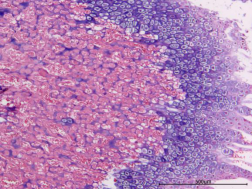

正常組、骨折組

圖1 HE染色圖 40X

樣本中細胞核被蘇木精染成藍色;細胞質(zhì)被伊紅染成深淺不同的粉紅色至深紅色。

蘇木精-伊紅染色法簡稱HE染色法,是最常用的染色方法。蘇木精(hematoxylin)是陽離子染料,能夠?qū)⒓毎藘?nèi)的嗜堿性物質(zhì)染成藍紫色。伊紅(eosin)是陰離子染料,能夠?qū)⒓毎|(zhì)和膠原纖維等染成粉紅色。